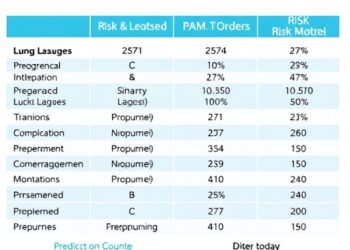

Risk Model Predicts Multiple Lung Lavages in Children

In the realm of pediatric respiratory diseases, necrotizing pneumonia (NP) stands out as a particularly severe and complex condition. Recently,...